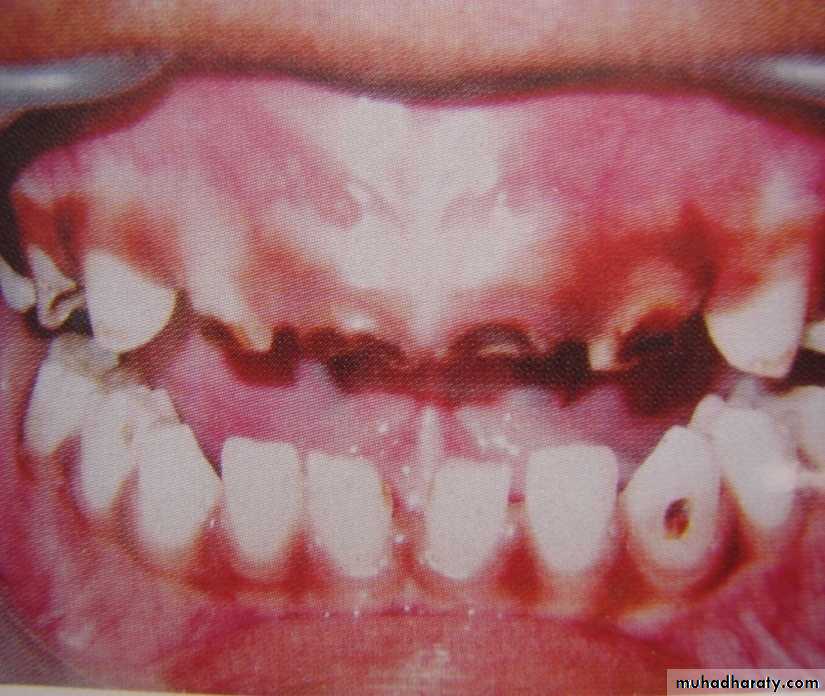

RAMPANT DENTAL CARIES

Characterized by sudden, rapid destruction of teeth affecting even relatively caries free surfaces like proximal and cervical surfaces of mandibular teeth.

10 or more carious lesions over a one year period is characteristic of rampant caries.

Prominently observed in deciduous dentition of young children and permanent dentition of teenagers.

Dietary factors like high carbohydrate intake etc as well as physiological factors affecting saliva are major contributors to etiology of rampant caries.

NURSING BOTTLE CARIES

• Nursing bottle containing milk, milk formula or sweetened water.• Breast feeding

• Sugar or honey sweetened pacifiers

Usually, the above aids are used at sleeping time after one year of age.

Clinically seen as widespread caries of the 4 maxillary incisors followed by 1st molars and then canines.Absence of caries in mandibular teeth distinguishes it from ordinary rampant caries.

If milk or other carbohydrates are rapidly cleared from mouth, they aren’t cariogenic, but if they pool in the mouth, then they can cause rampant caries.

Mandibular teeth usually escape the process as the pooled milk or sweet products are washed away by saliva